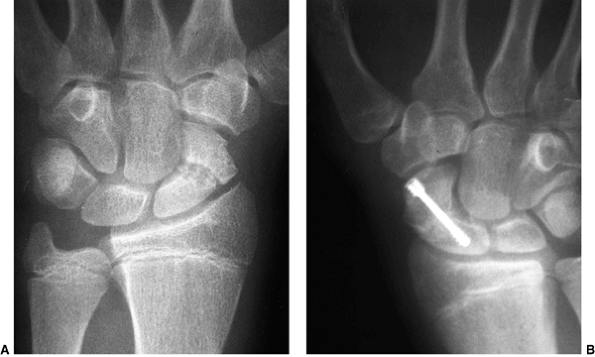

![]() |

Figure 23.8 A:

Preoperative radiograph of a congenital radioulnar synostosis. There is complete fusion of the proximal radius and ulna, and posterior dislocation of the radial head. The entire ulna is mildly hypoplastic. B: Postoperative radiograph of a derotation corrective osteotomy for this patient. A longitudinal wire is passed down the medullary canal of the ulna across the synostosis site. This Kirschner wire starts from the proximal ulnar apophysis. The osteotomy cut is performed through the synostosis. The transfixing wire is obliquely placed to secure the corrective derotation to a position of 0 to 20 degrees of pronation. |